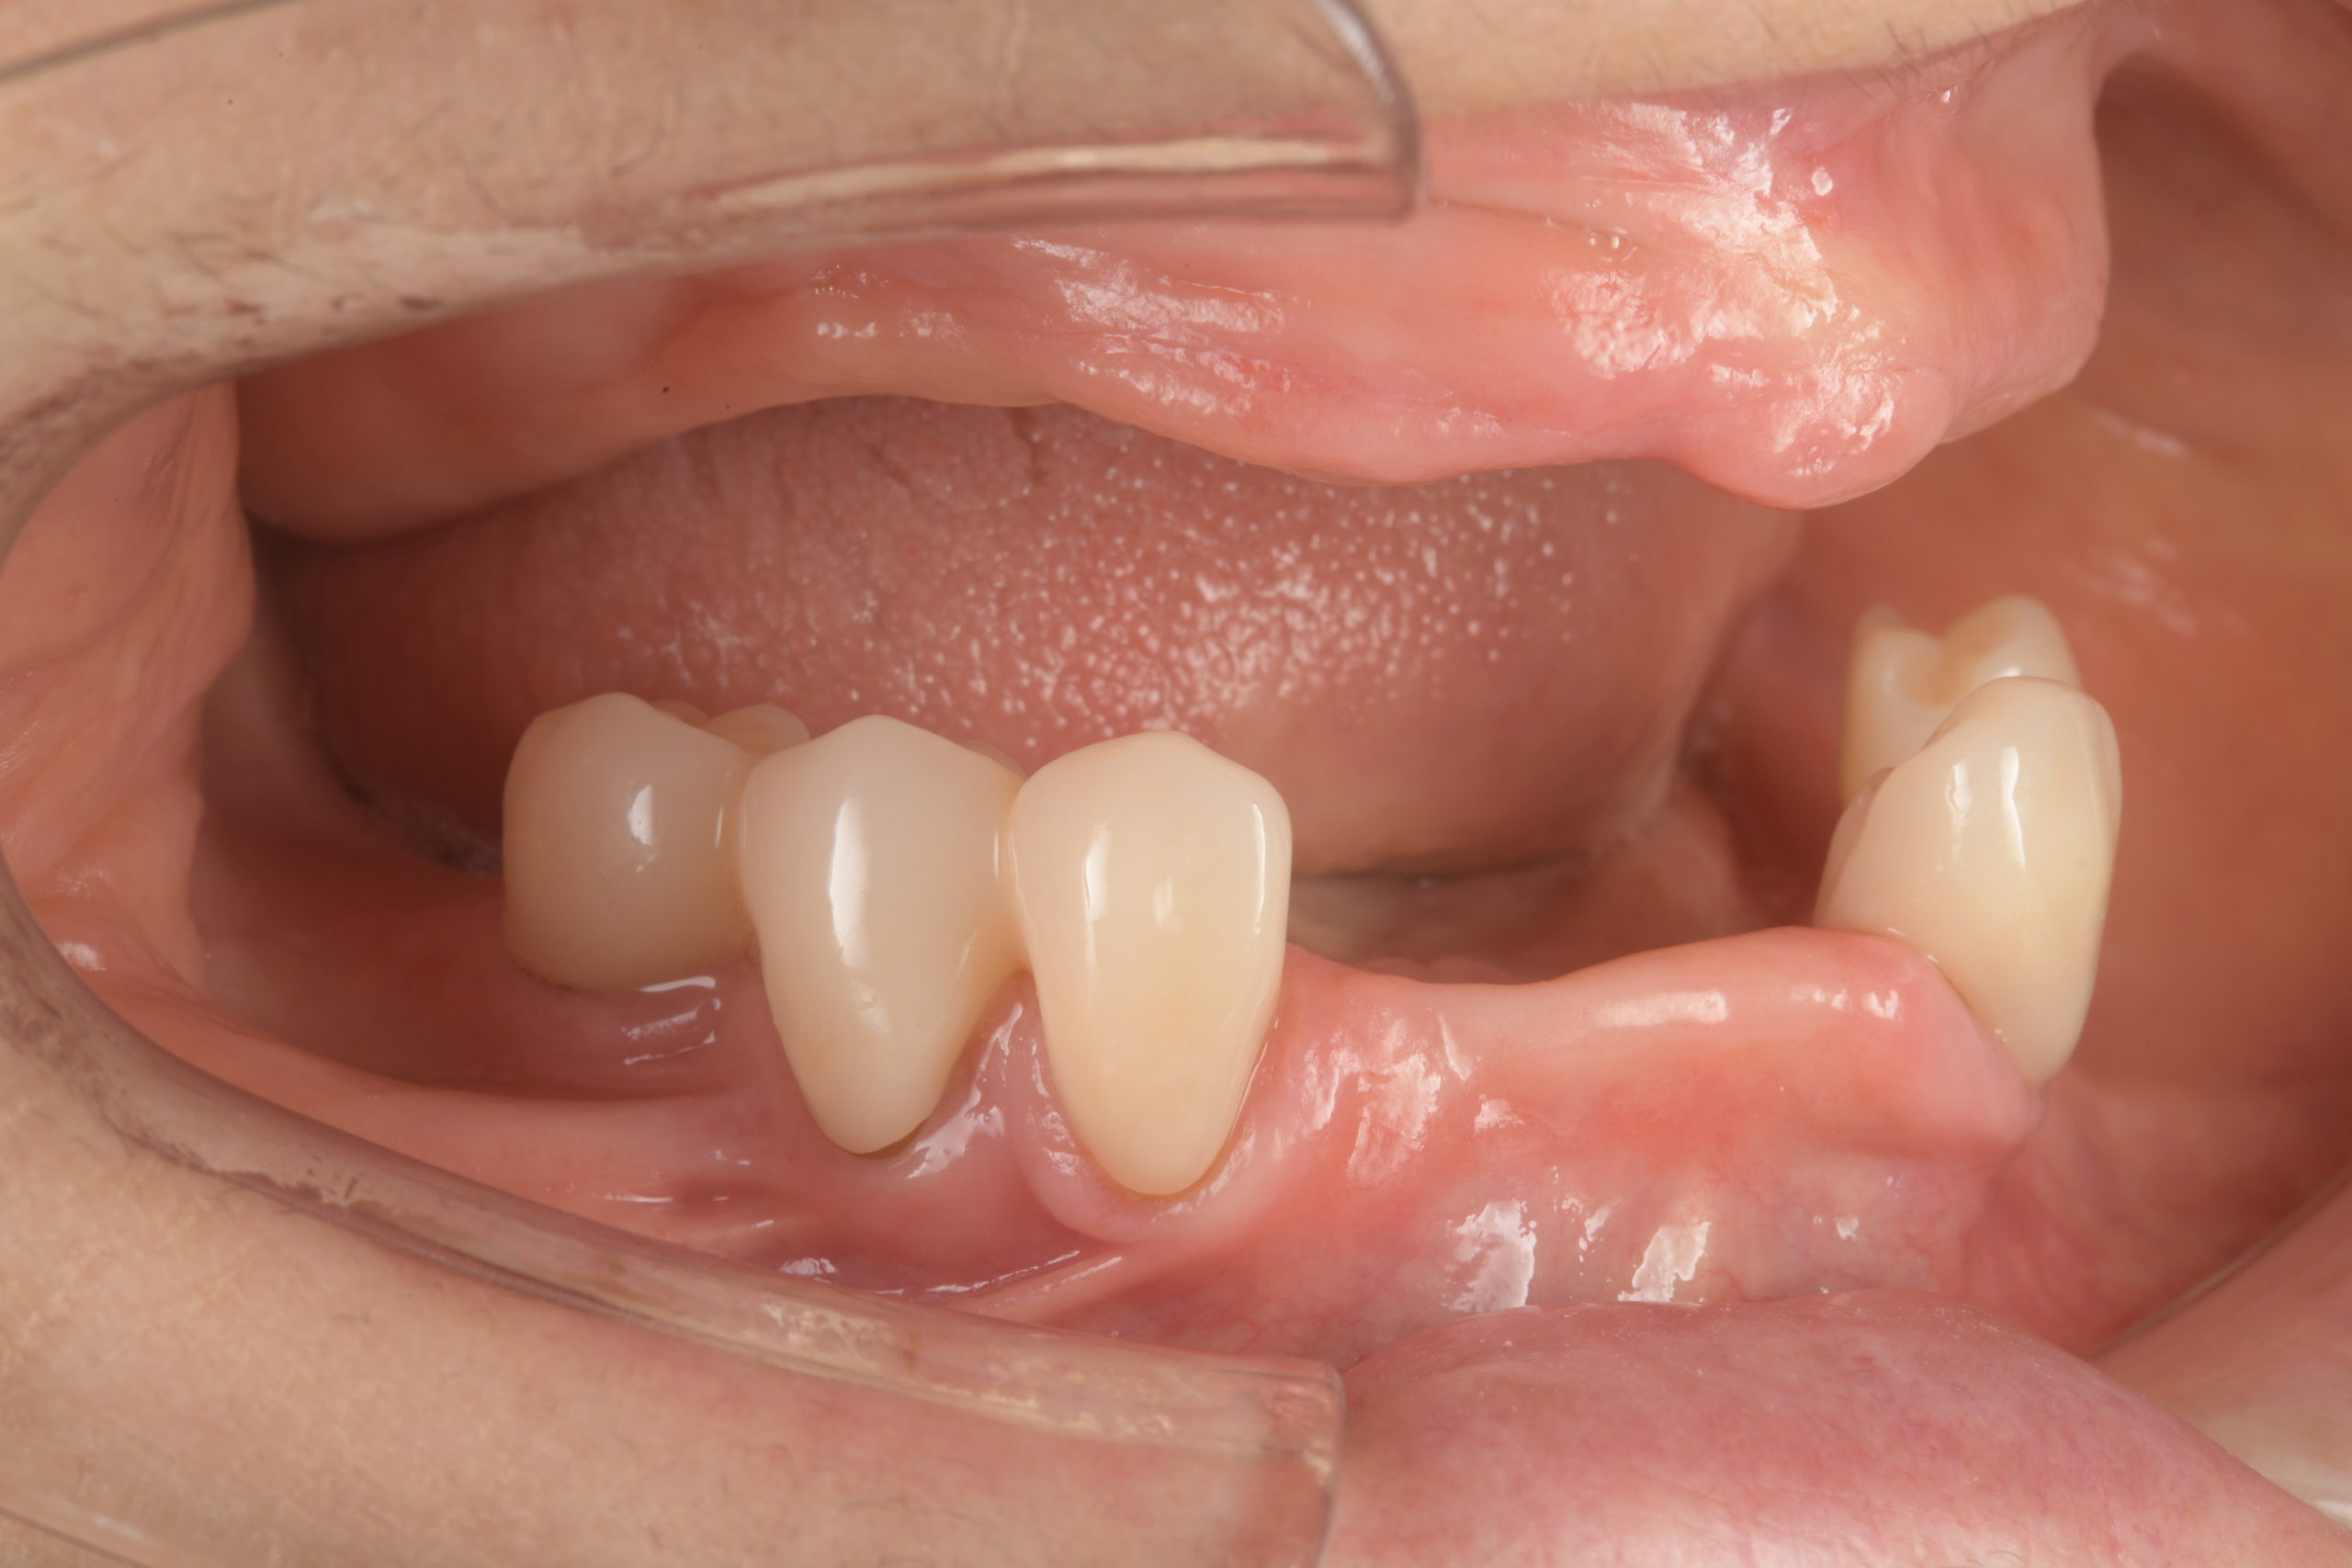

治療前